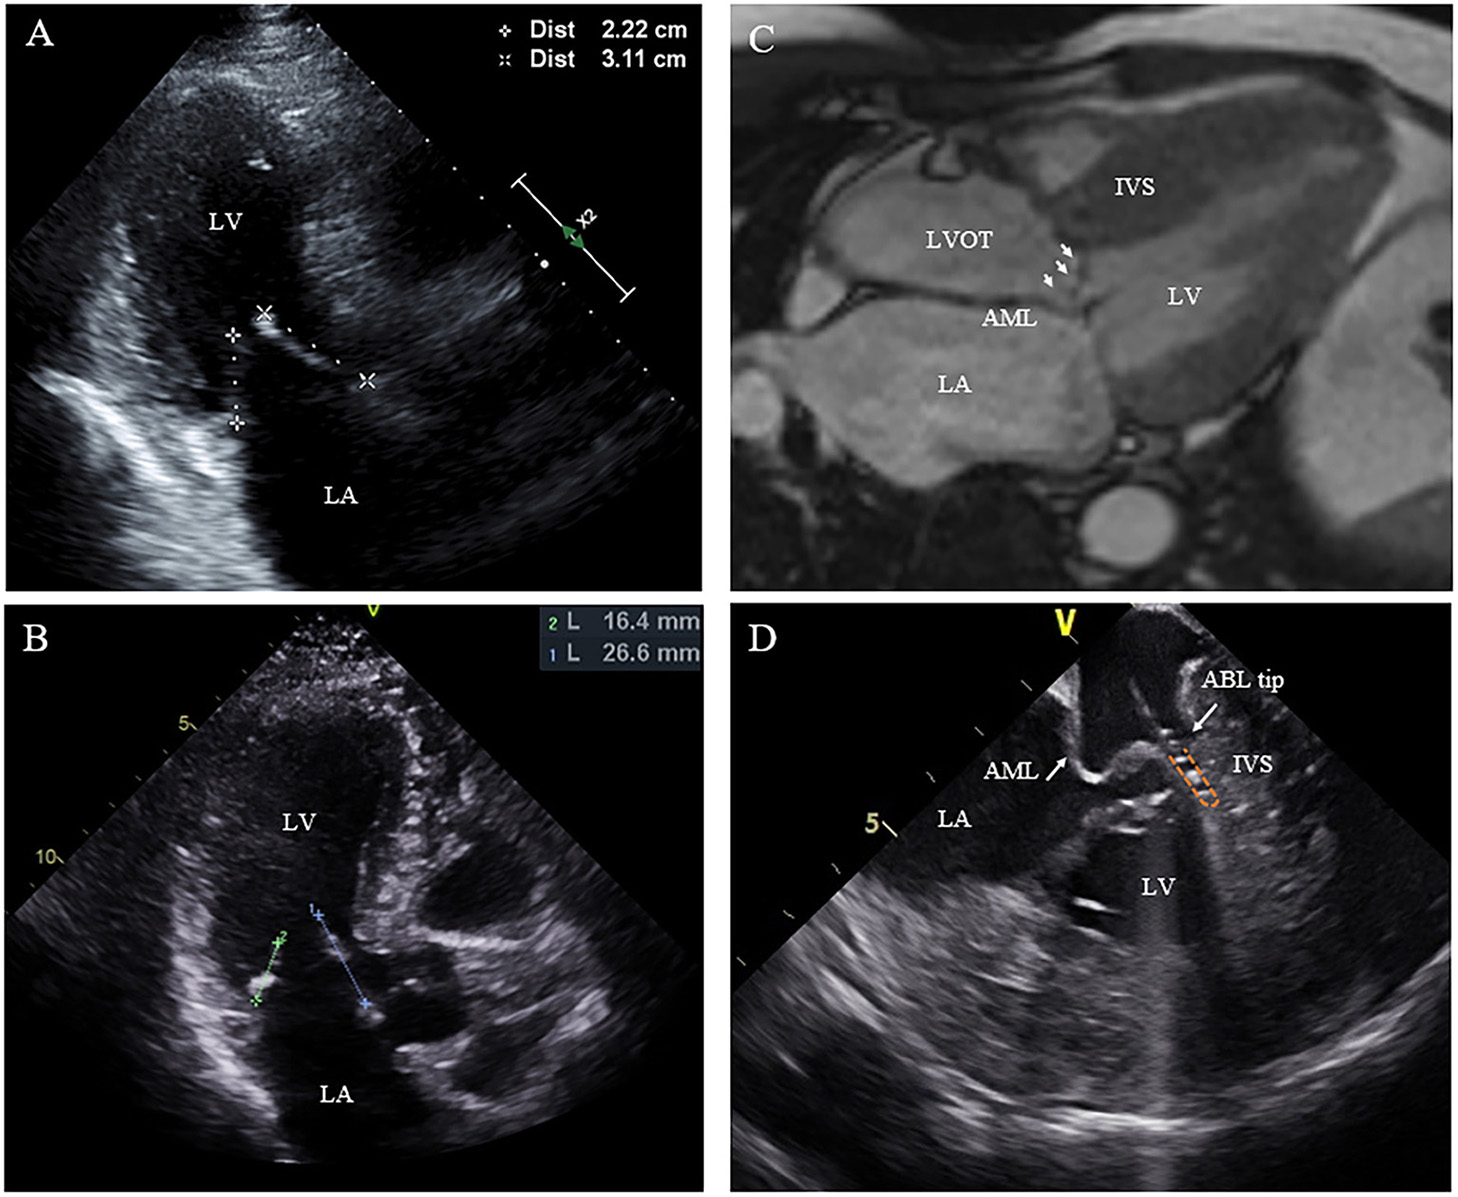

Figure 3

Morphologic abnormalities of mitral valve contributing to outflow tract obstruction. (A,B) The length of the AML was measured by echocardiography in diastole on the apical three-chamber view. (C) Extraordinarily long anterior mitral valve leaflet on CMR. (D) On live ICE screen, the AML (white arrow) is reflexed and attached to IVS during systole and pats on the ablation catheter tip during procedure. AML, anterior mitral leaflet.

Nineteen of the 20 patients underwent ablation successfully, while one patient with RBBB presented with transient complete AVB at the beginning of RF ablation. The procedure was discontinued without further ablation. SAM can be observed in all patients on ICE with the AML either touching or nearly touching the interventricular septum. For patient No. 12, an extraordinarily long and flexible mitral leaflet was observed with real-time ICE. The AML was reflexed and attached to the IVS during systole (Figure 3D). RF energy was delivered only in the same region where the AML flapped. Trans-atrial septal access was used in five patients to achieve more stable catheter-tissue contact. After ablation, significant tissue edema can be observed on the real-time ICE image (Figure 1E). Invasive resting LVOT gradients were measured before and after the procedure and decreased significantly from 88.9 ± 30.5 to 33.5 ± 30.1 mmHg (p < 0.001). The mean procedure time was 208.4 ± 49.4 min and the mean X-ray exposure time was 13.9 ± 7.2 min. A mean of 15.2 ± 8.1 min of RF energy was applied. A mean depth of 4.3 ± 1.2 mm tissue damage was created. Ablated area was 2.9 ± 1.4 cm2, representing 12.7 ± 5.6% of total septum endocardial surface (Figure 1D).

In addition to left ventricular hypertrophy, structural abnormalities of the mitral valve and sub-mitral apparatus, such as leaflet elongation and anterior displacement of the papillary muscles also contribute to SAM pathophysiology (25). The average length of AML is longer in HOCM patients (34 vs. 24 mm). For those with an extraordinarily elongated AML (>30 mm), the residual portion often extends past the point of coaptation. Without the constraint of the LV–left atrium pressure difference, it can freely move with LV flow, even at low velocity. Late diastolic and early systolic flow then pushes the protruding leaflets into apposition with the septum (21, 22, 26). Meanwhile, the anterior displacement of PM exacerbates the magnitude of obstruction. There is closer proximity between the DPM and the hypertrophied septum especially the mid-septum and even contact each other at end of systole (Figure 2). This malformation positions mitral leaflets anteriorly into the flow stream cause a crucial overlap of the inflow and outflow portions of the LV that predisposes to SAM. Sherrid et al. indicated that a simple septal reduction procedure was not enough if AML > 30 mm and (or) DPM exist and resect—plicate—release (RPR) operation was required to alleviate LVOT gradients (25). Consistent with this observation, the reduction of gradient in patients with elongated AML or DPM is significantly lower (Figure 6). In our approach, RF energy was applied to create a localized reduction in contractility responsible for the dynamic obstruction. The maximal depth of penetration was measured by ICE and a mean depth of 4.3 ± 1.2 mm tissue damage was created during ablation. There was a non-significant reduction of the septal thickness after ablation. The structural abnormalities of mitral valve and papillary muscle are nearly impossible to rectify by RF ablation. Therefore, for patients with AMLs > 30 mm and (or) DPM, surgery with resect-plicate-release operation should be preferred.